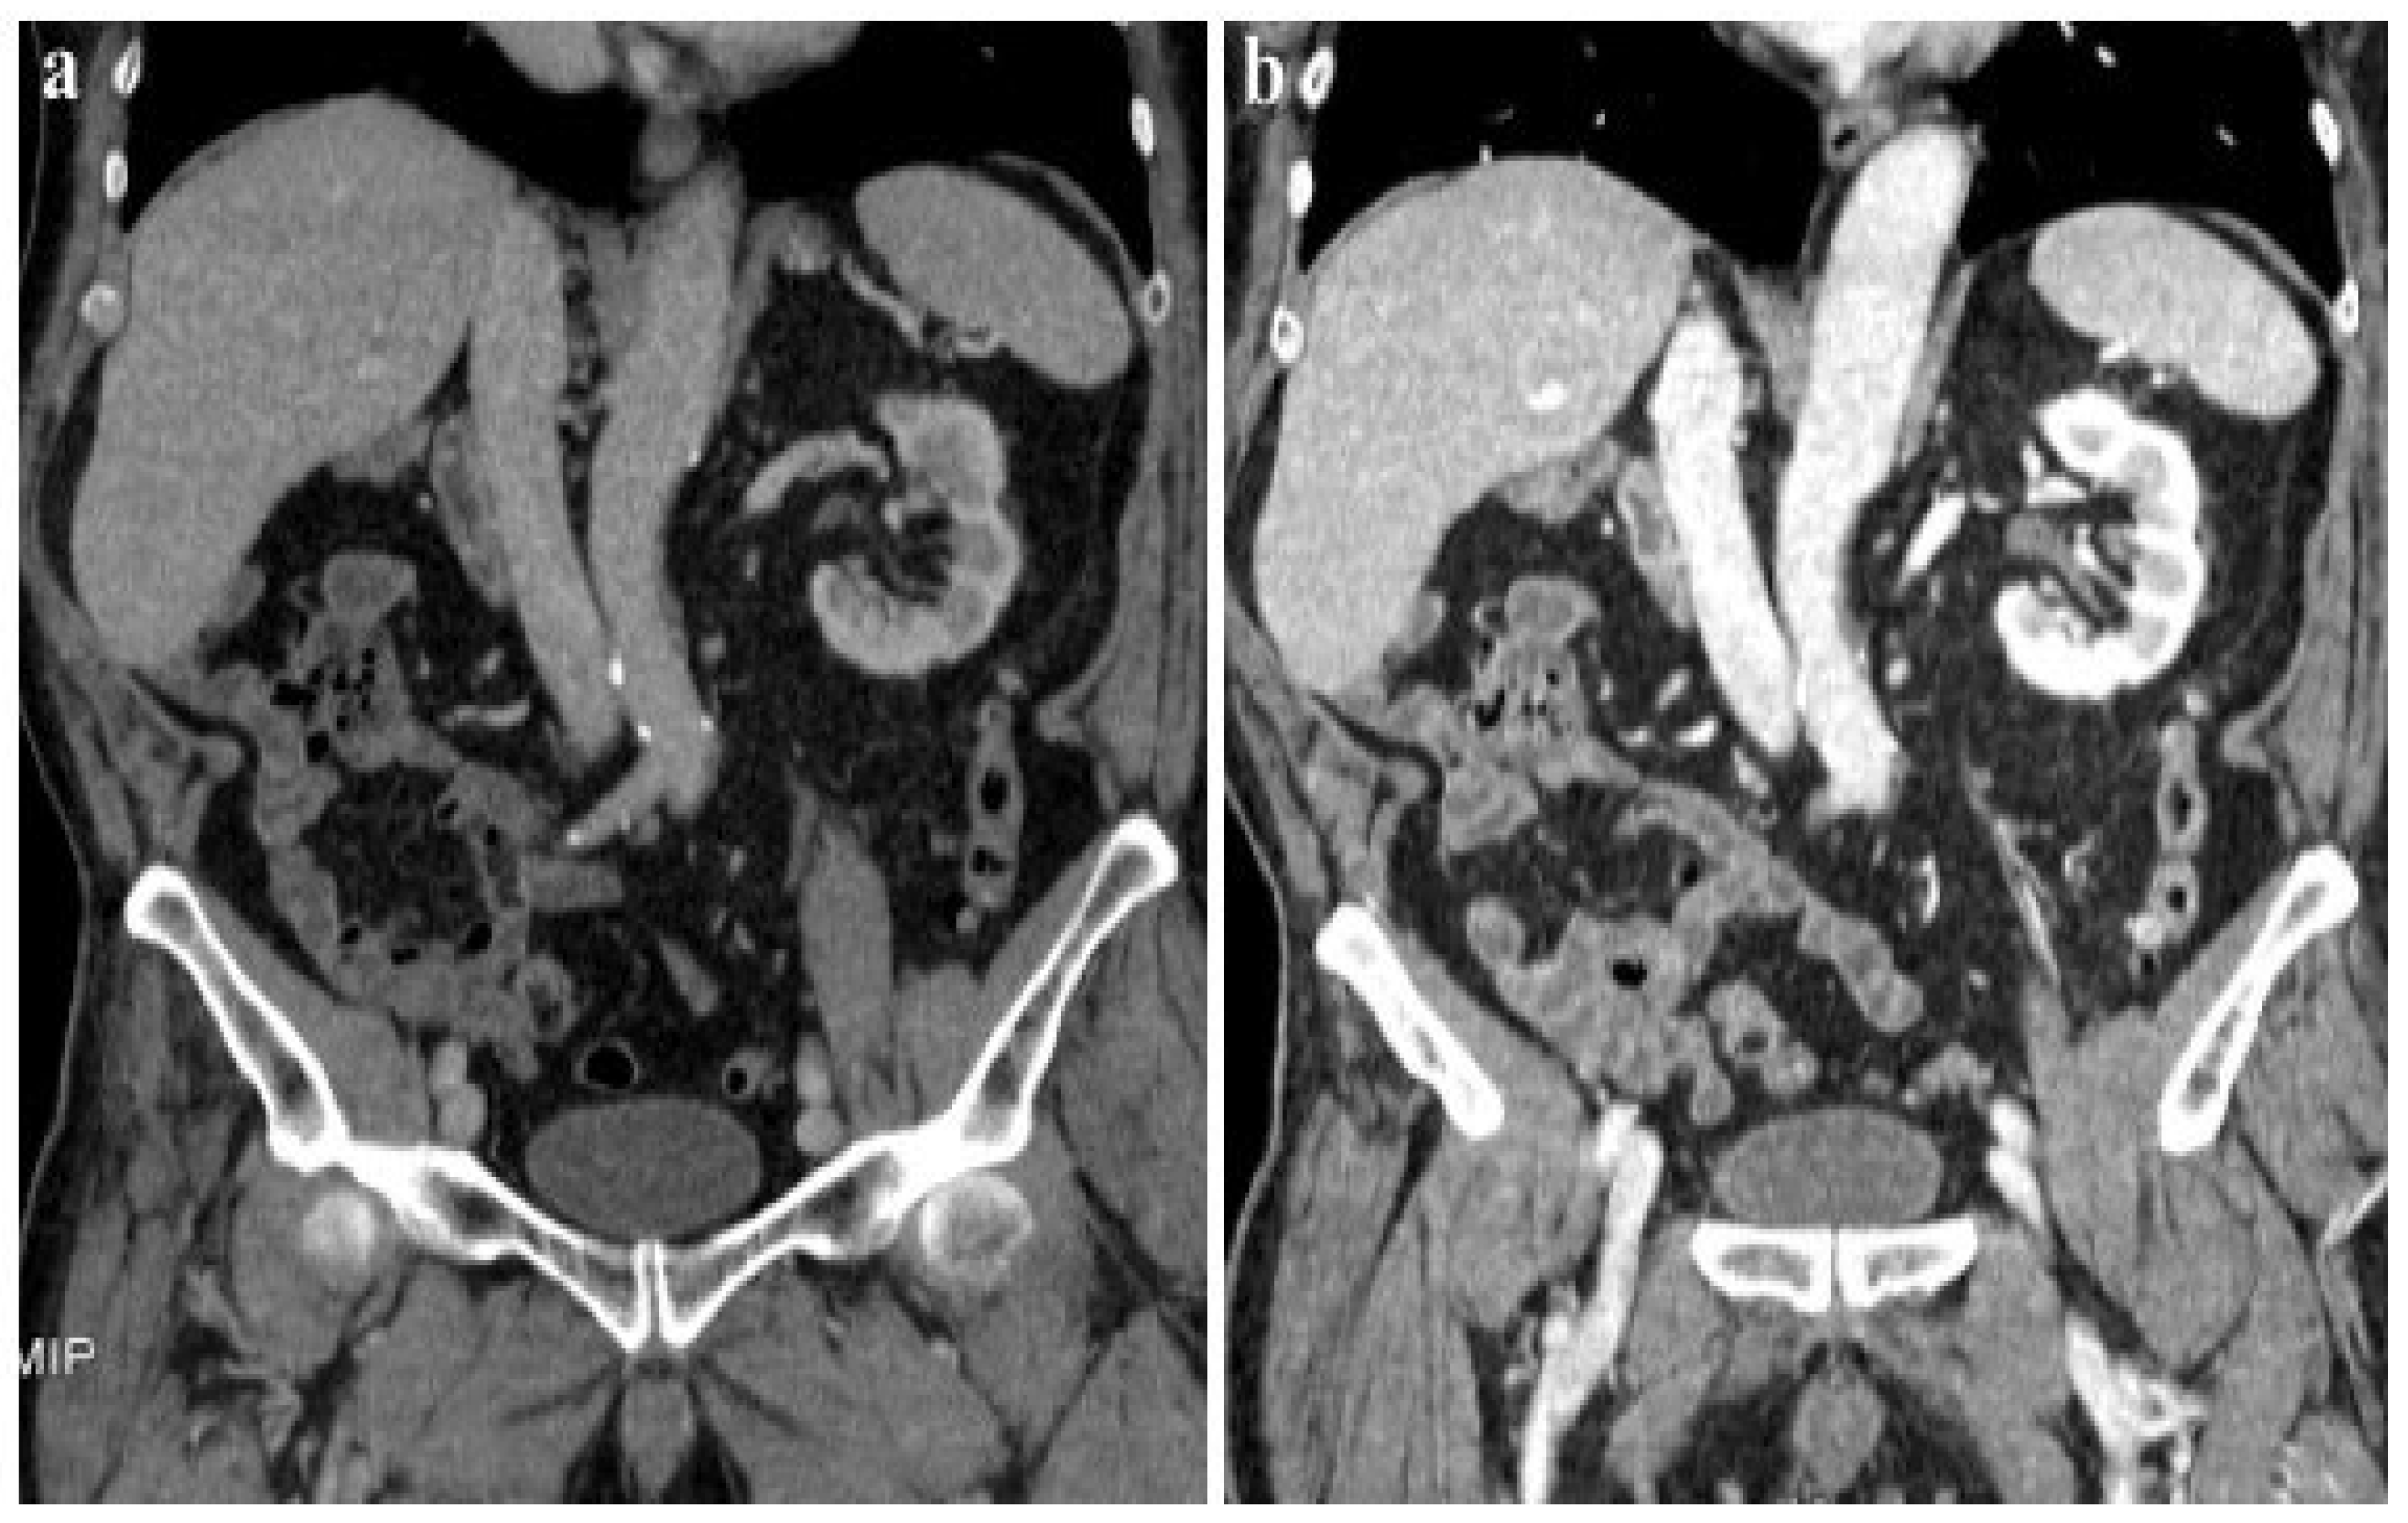

According to our results, no significant differences were found in vascular and parenchymal enhancement in DECT imaging with a reduced CM protocol as compared to conventional SECT with a standard weight-based CM protocol (Figure 2).

Figure 2.

A 120 kVp SECT performed with a standard iodine dose (a) compared to VMI at 40 KeV (DECT) performed with a reduced iodine dose (b) in a 80-year-old patient with impaired renal function. VMI (b) allows a significative reduction in CM administration and improved image quality compared to 120 kVp SECT (a).